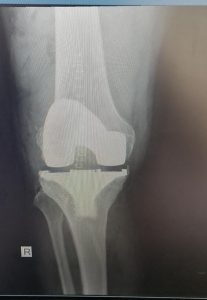

KNEE REPLACEMENT

As the knee ages it may come to a point where cartilage has eroded away to expose bone. Bone grinding on bone as a person is walking is very painful. Fortunately orthopaedic science has evolved to a solution whereby the knee can be replaced with a mechanical prosthesis.

Presently, the results are generally very good with excellent pain relief and mobility after the operation. Longevity of the prosthesis has improved to a point where the 10 year survival is more than 95% in some series.

As all surgery, the procedure is not entirely risk free. Deep venous thrombosis at 1% incidence and infection at 0.4% are most common complications, but stiffness, bleeding, nerve injury etc. can occur.

Below see the pre operative pictures of a normal knee, a diseased knee and a replaced knee.